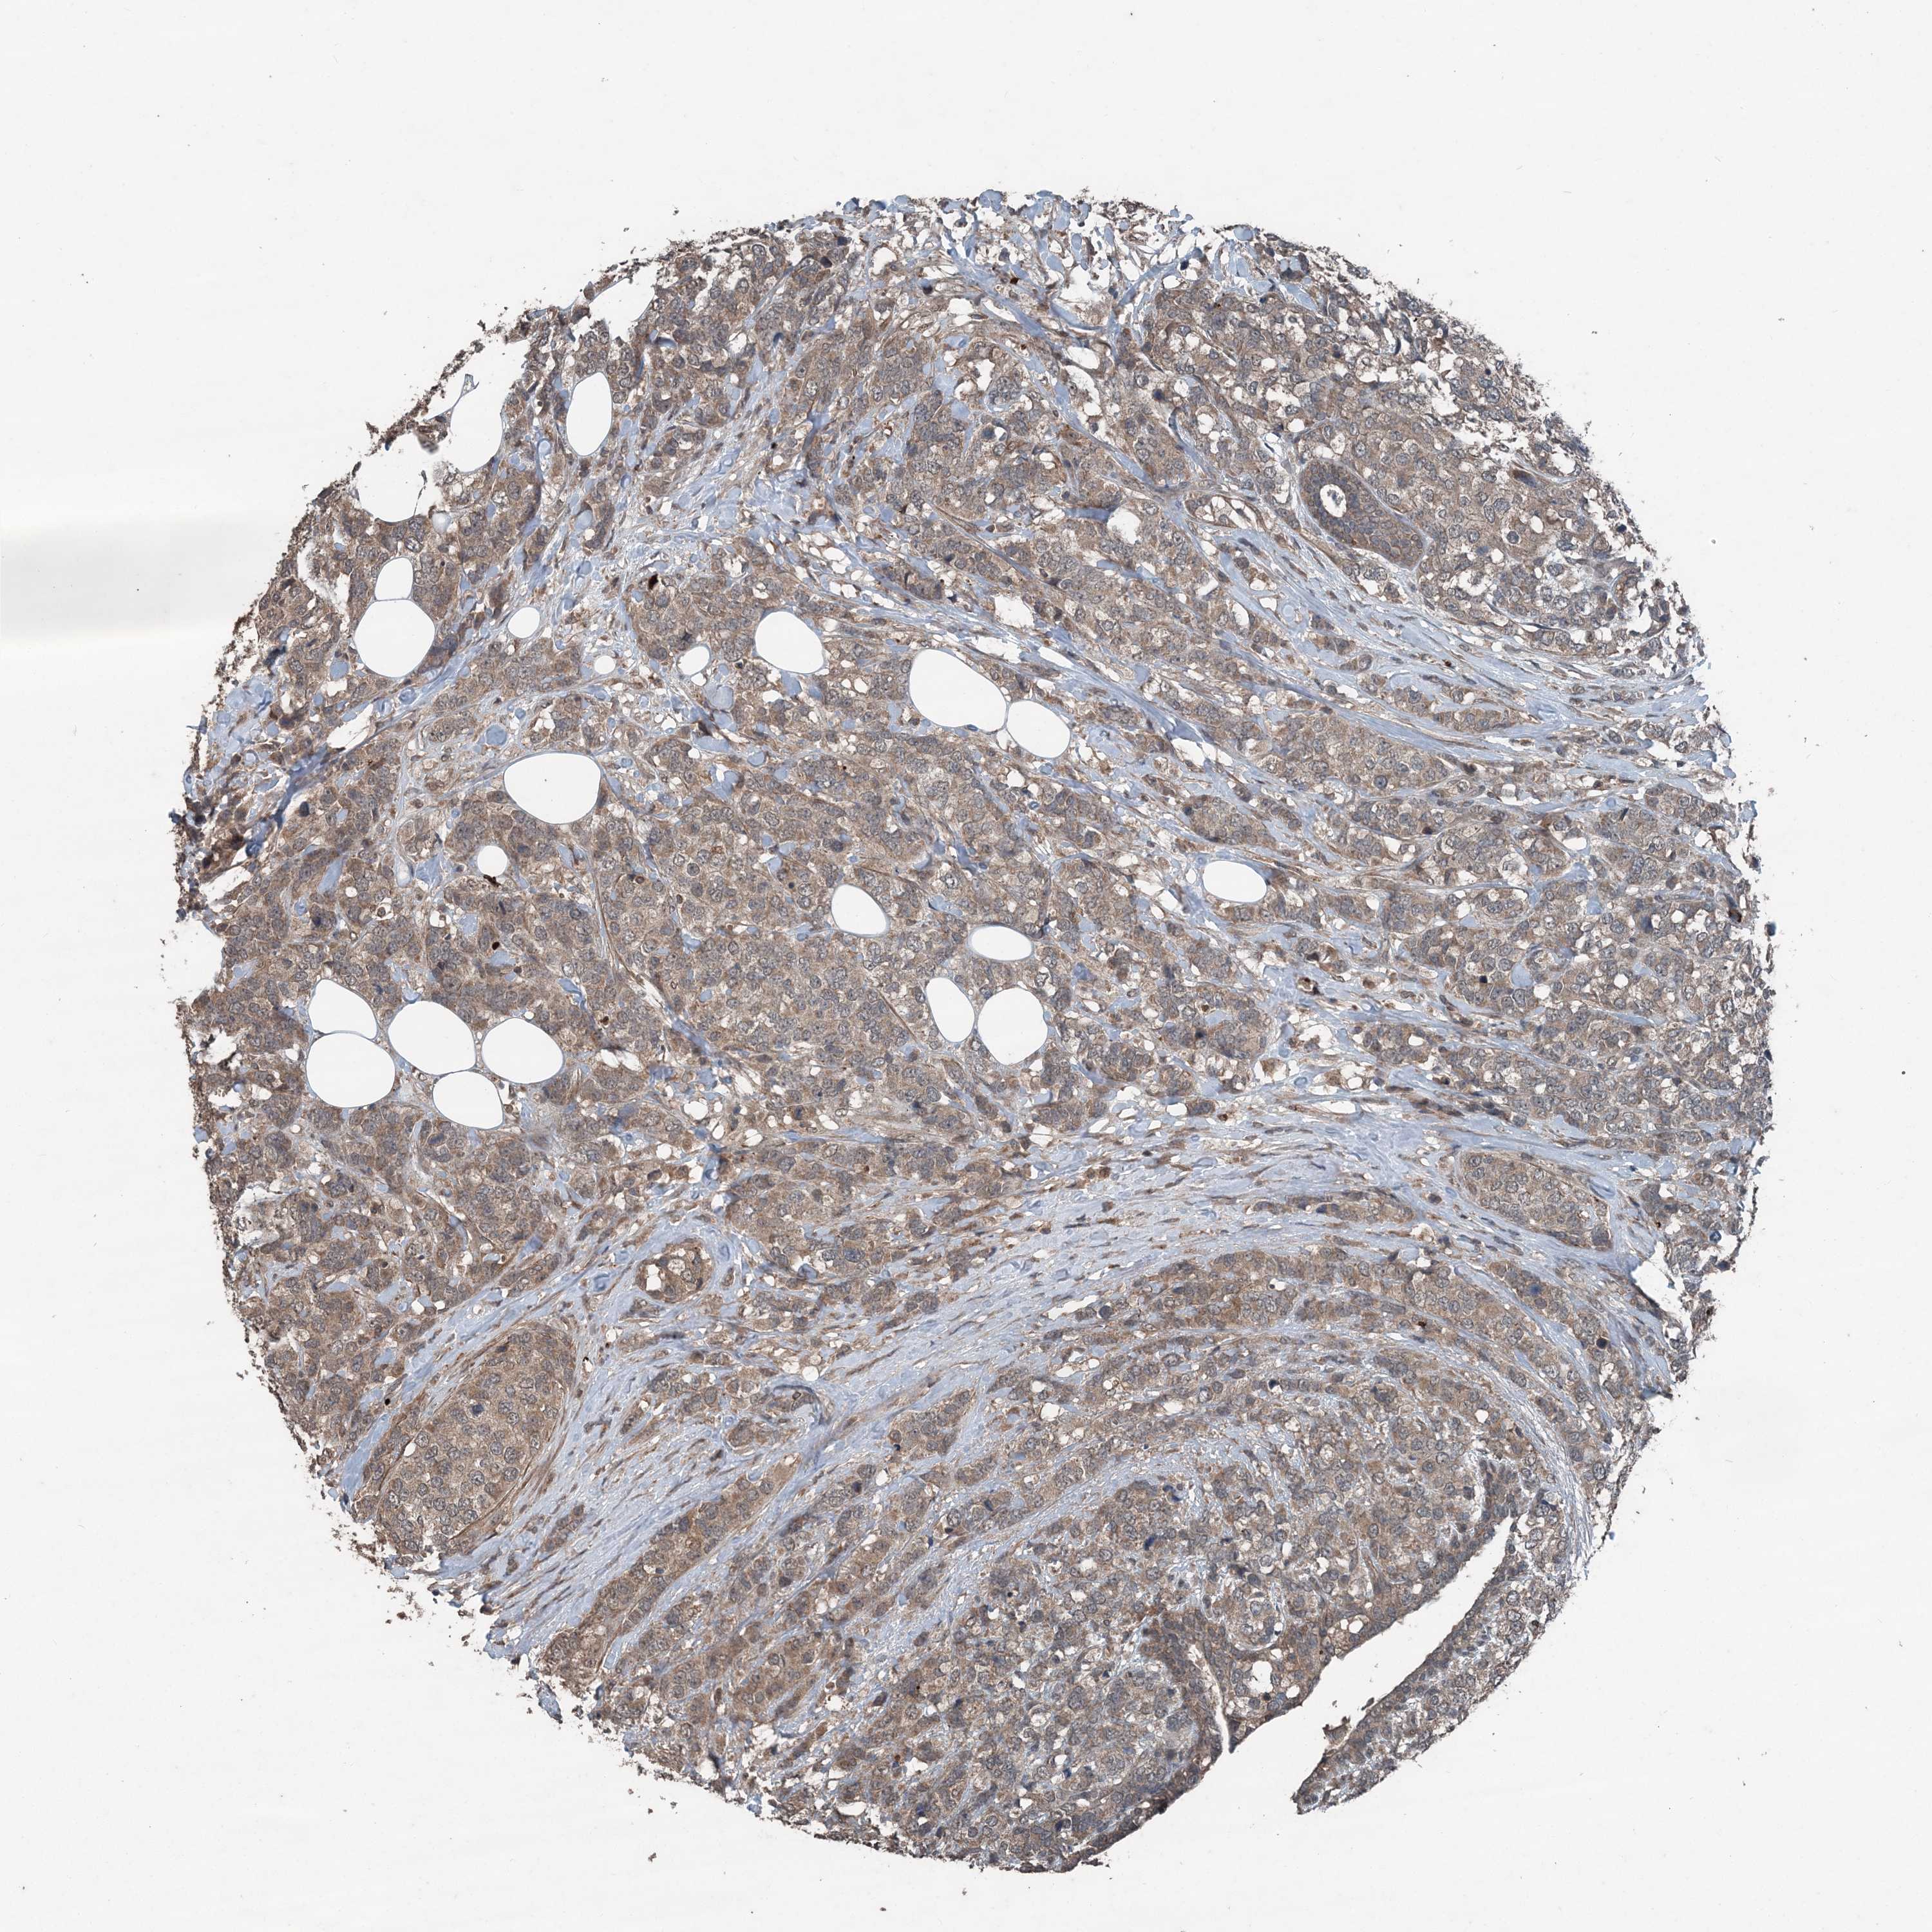

CANCER BREAST CANCER Show tissue menu

BRCA TCGA BRCA VALIDATION PROTEIN EXPRESSION

ANTIBODIES

AND

VALIDATION